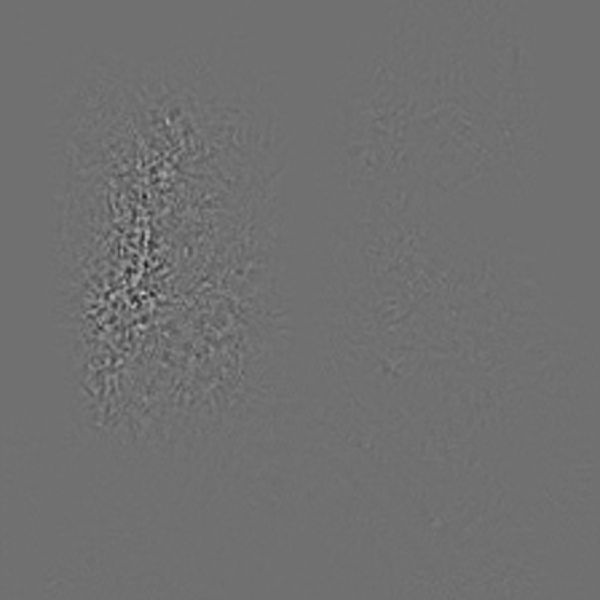

2.2 Guided Backpropagation

Guided Backpropagation was first introduced in [8] and works by first propagating the input through the entire model similar to Grad-CAM. In a second step the output is then backpropagated through the entire model. However only the non-negative gradients are passed to the next layer as negative gradients correspond to suppressed pixels deemed not relevant by the authors. The result is a noise-like image depicting the model attention as shown in figure 5. The advantage of Guided Backpropagation is that the attention is pixel-precise. The downsides are that it is neither class nor layer discriminant.

Refer to caption

Figure 5: The resulting Guided Backpropagation attention maps from the input images.